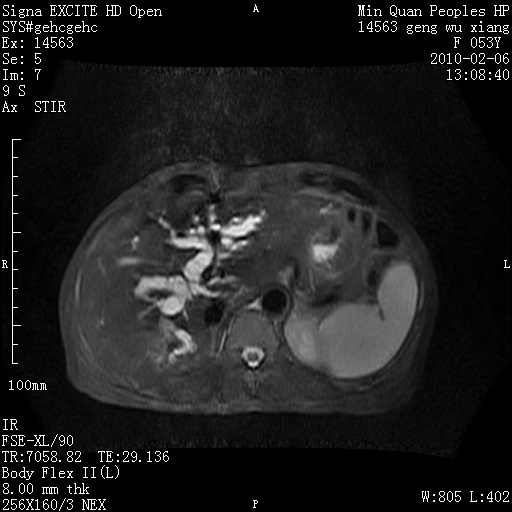

标题: MRI2762:胆道梗阻原因?

f,53y,全身黄染多日。

高位胆道梗阻 胆管癌可能性大

支持 高位胆道梗阻 胆管癌可能性大。